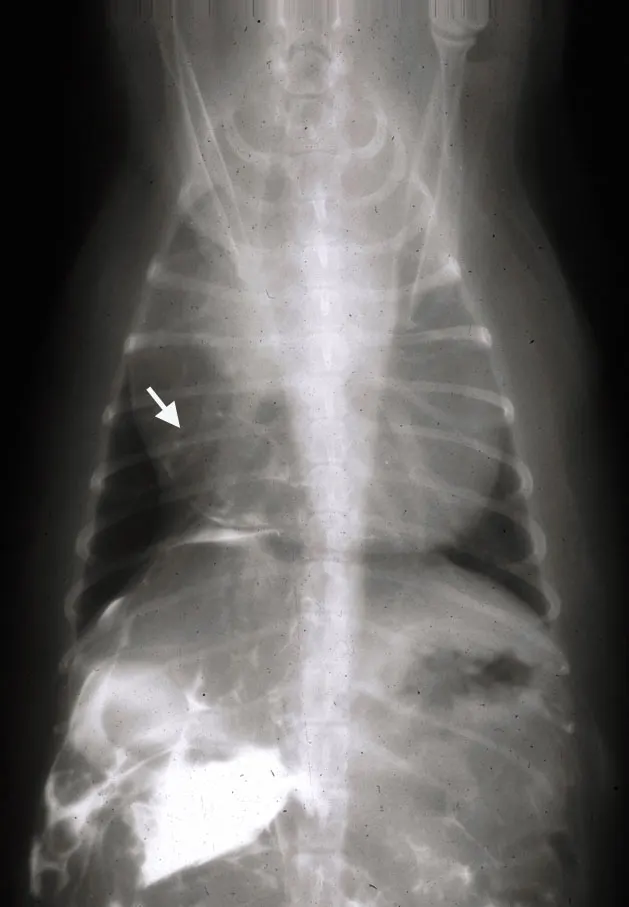

Diagnosis of diaphragmatic hernias is most easily accomplished with thoracic radiographs. The presence of bowel loops (A) or other abdominal organs within the thorax is diagnostic for diaphragmatic hernia. Sensitivity of radiographic detection of diaphragmatic hernias can be increased by performing a positive-contrast gastrointestinal study using barium. Alternatively, a positive-contrast peritoneogram can be done by injecting sterile, water-soluble contrast material into the abdominal cavity (about 2.2 ml/kg diluted with an equal volume of sterile saline).

A positive test occurs when contrast material can be observed within the thoracic cavity. The contrast agent is apparent in the pericardial sac (B; arrow) of this congenital peritoneopericardial diaphragmatic hernia. Holding the animal with the hindlegs elevated may facilitate movement of contrast matter through the hernia. The diaphragmatic rent may be sealed by omentum; thus, a negative result of this study does not rule out diaphragmatic hernia. Ultrasonography may also be useful to detect abdominal viscera within the thorax.